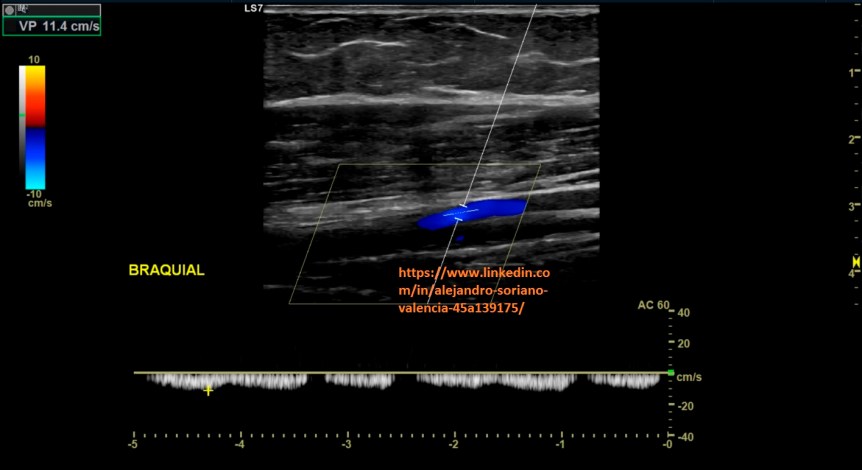

o Braquiales.

Brazo extendido en posición anterior. Nos servirá de guía la

arteria braquial para identificar las dos venas adyacentes a ella.

Arm extended in anterior position. The brachial artery will guide us to identify the two veins adjacent to it.

7. Braquiales transversal.

8. Braquial longitudinal. Estudio triplex.